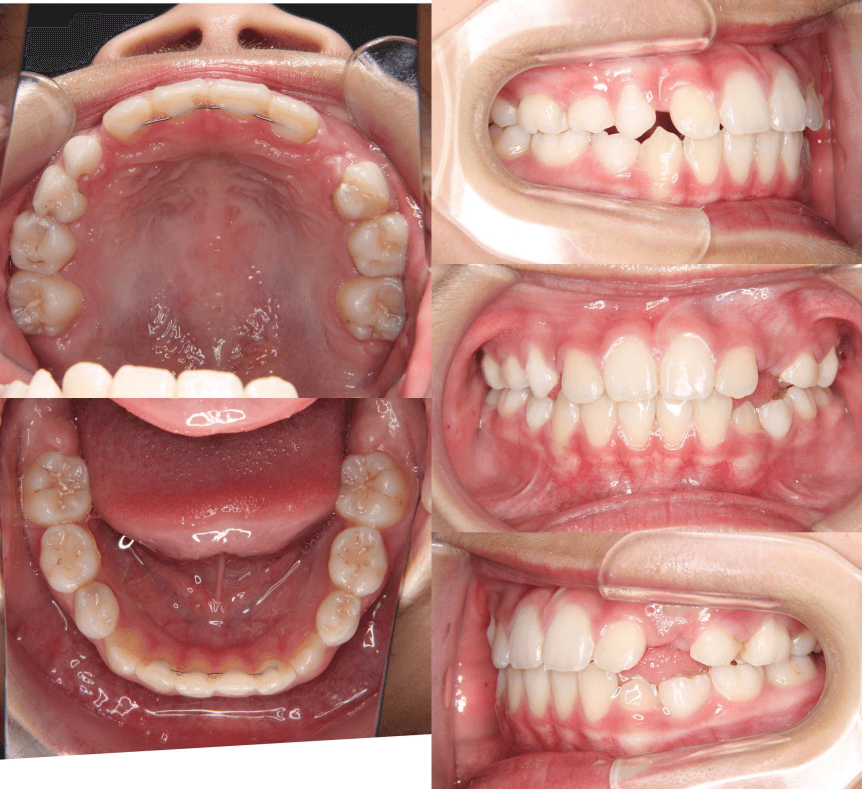

| 年齢・性別 | 8歳9ヶ月の男児 |

|---|---|

| 主訴 | 前歯の咬み合わせが逆になっており、歯根や歯肉への影響を懸念されて来院された患者様です。 |

| 治療期間・回数 | 3年7ヶ月・20回 |

| 費用 | 460,000円(税別) |